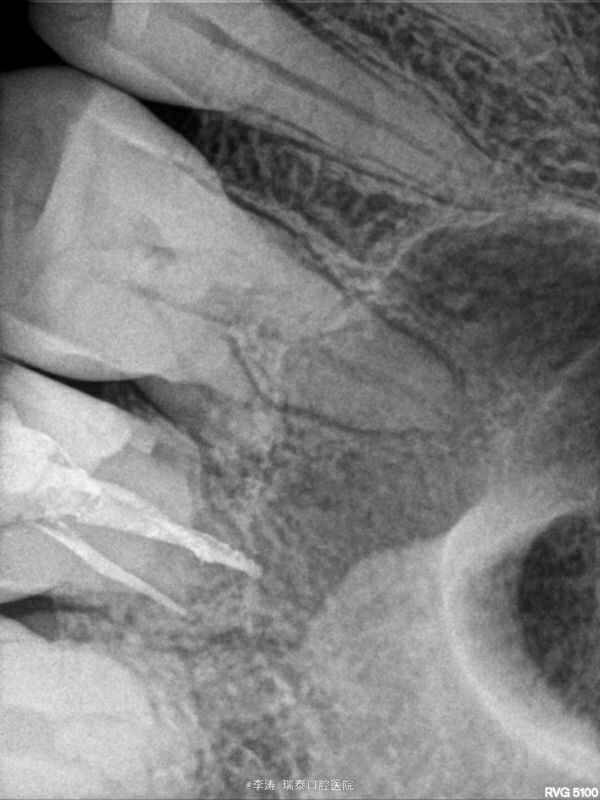

27牙伸长,松-,冷++,叩+-,近中邻面大面积龋坏,探及穿髓孔,x线片近中大面积龋坏近髓腔

27牙牙髓炎,行根管治疗 27磨短,测根长腭根11mm,近颊及远颊根15mm。置橡皮障,根管预备,根管消毒,根管充填。